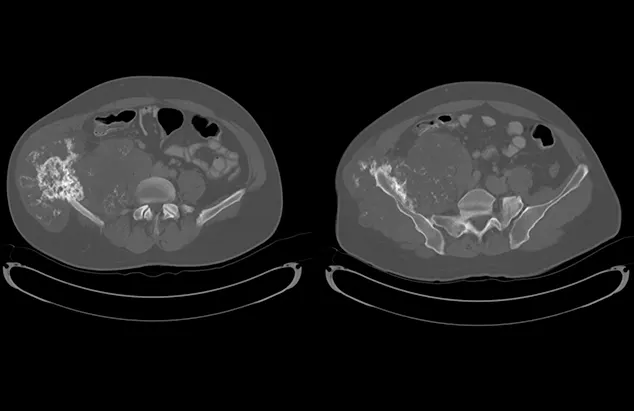

FIGURE 1

Axial (A) and coronal (B) CT images from the patient. An aggressive bone lesion arising from the left ilium, with extension to the surrounding soft tissues, can be seen.

CBC, serum chemistry profile, and urinalysis results were unremarkable. Three-view thoracic radiographs showed no evidence of gross metastatic disease. A CT scan of the chest, abdomen, and pelvis showed an aggressive bone lesion of the left ilium, compatible with osteosarcoma, with tumor extension to the surrounding soft tissue (Figure 1). A full-body bone scan was performed. Static images were obtained 2 hours after intravenous injection of Tc99m-MDP. There was marked uptake in the area of the primary tumor (ie, the left ilium). There was also a possible metastatic lesion in the left costal cartilages; however, careful review of the CT scan showed that the increased uptake of radiopharmaceutical at that site was most likely consistent with old trauma rather than metastatic disease (Figure 2).